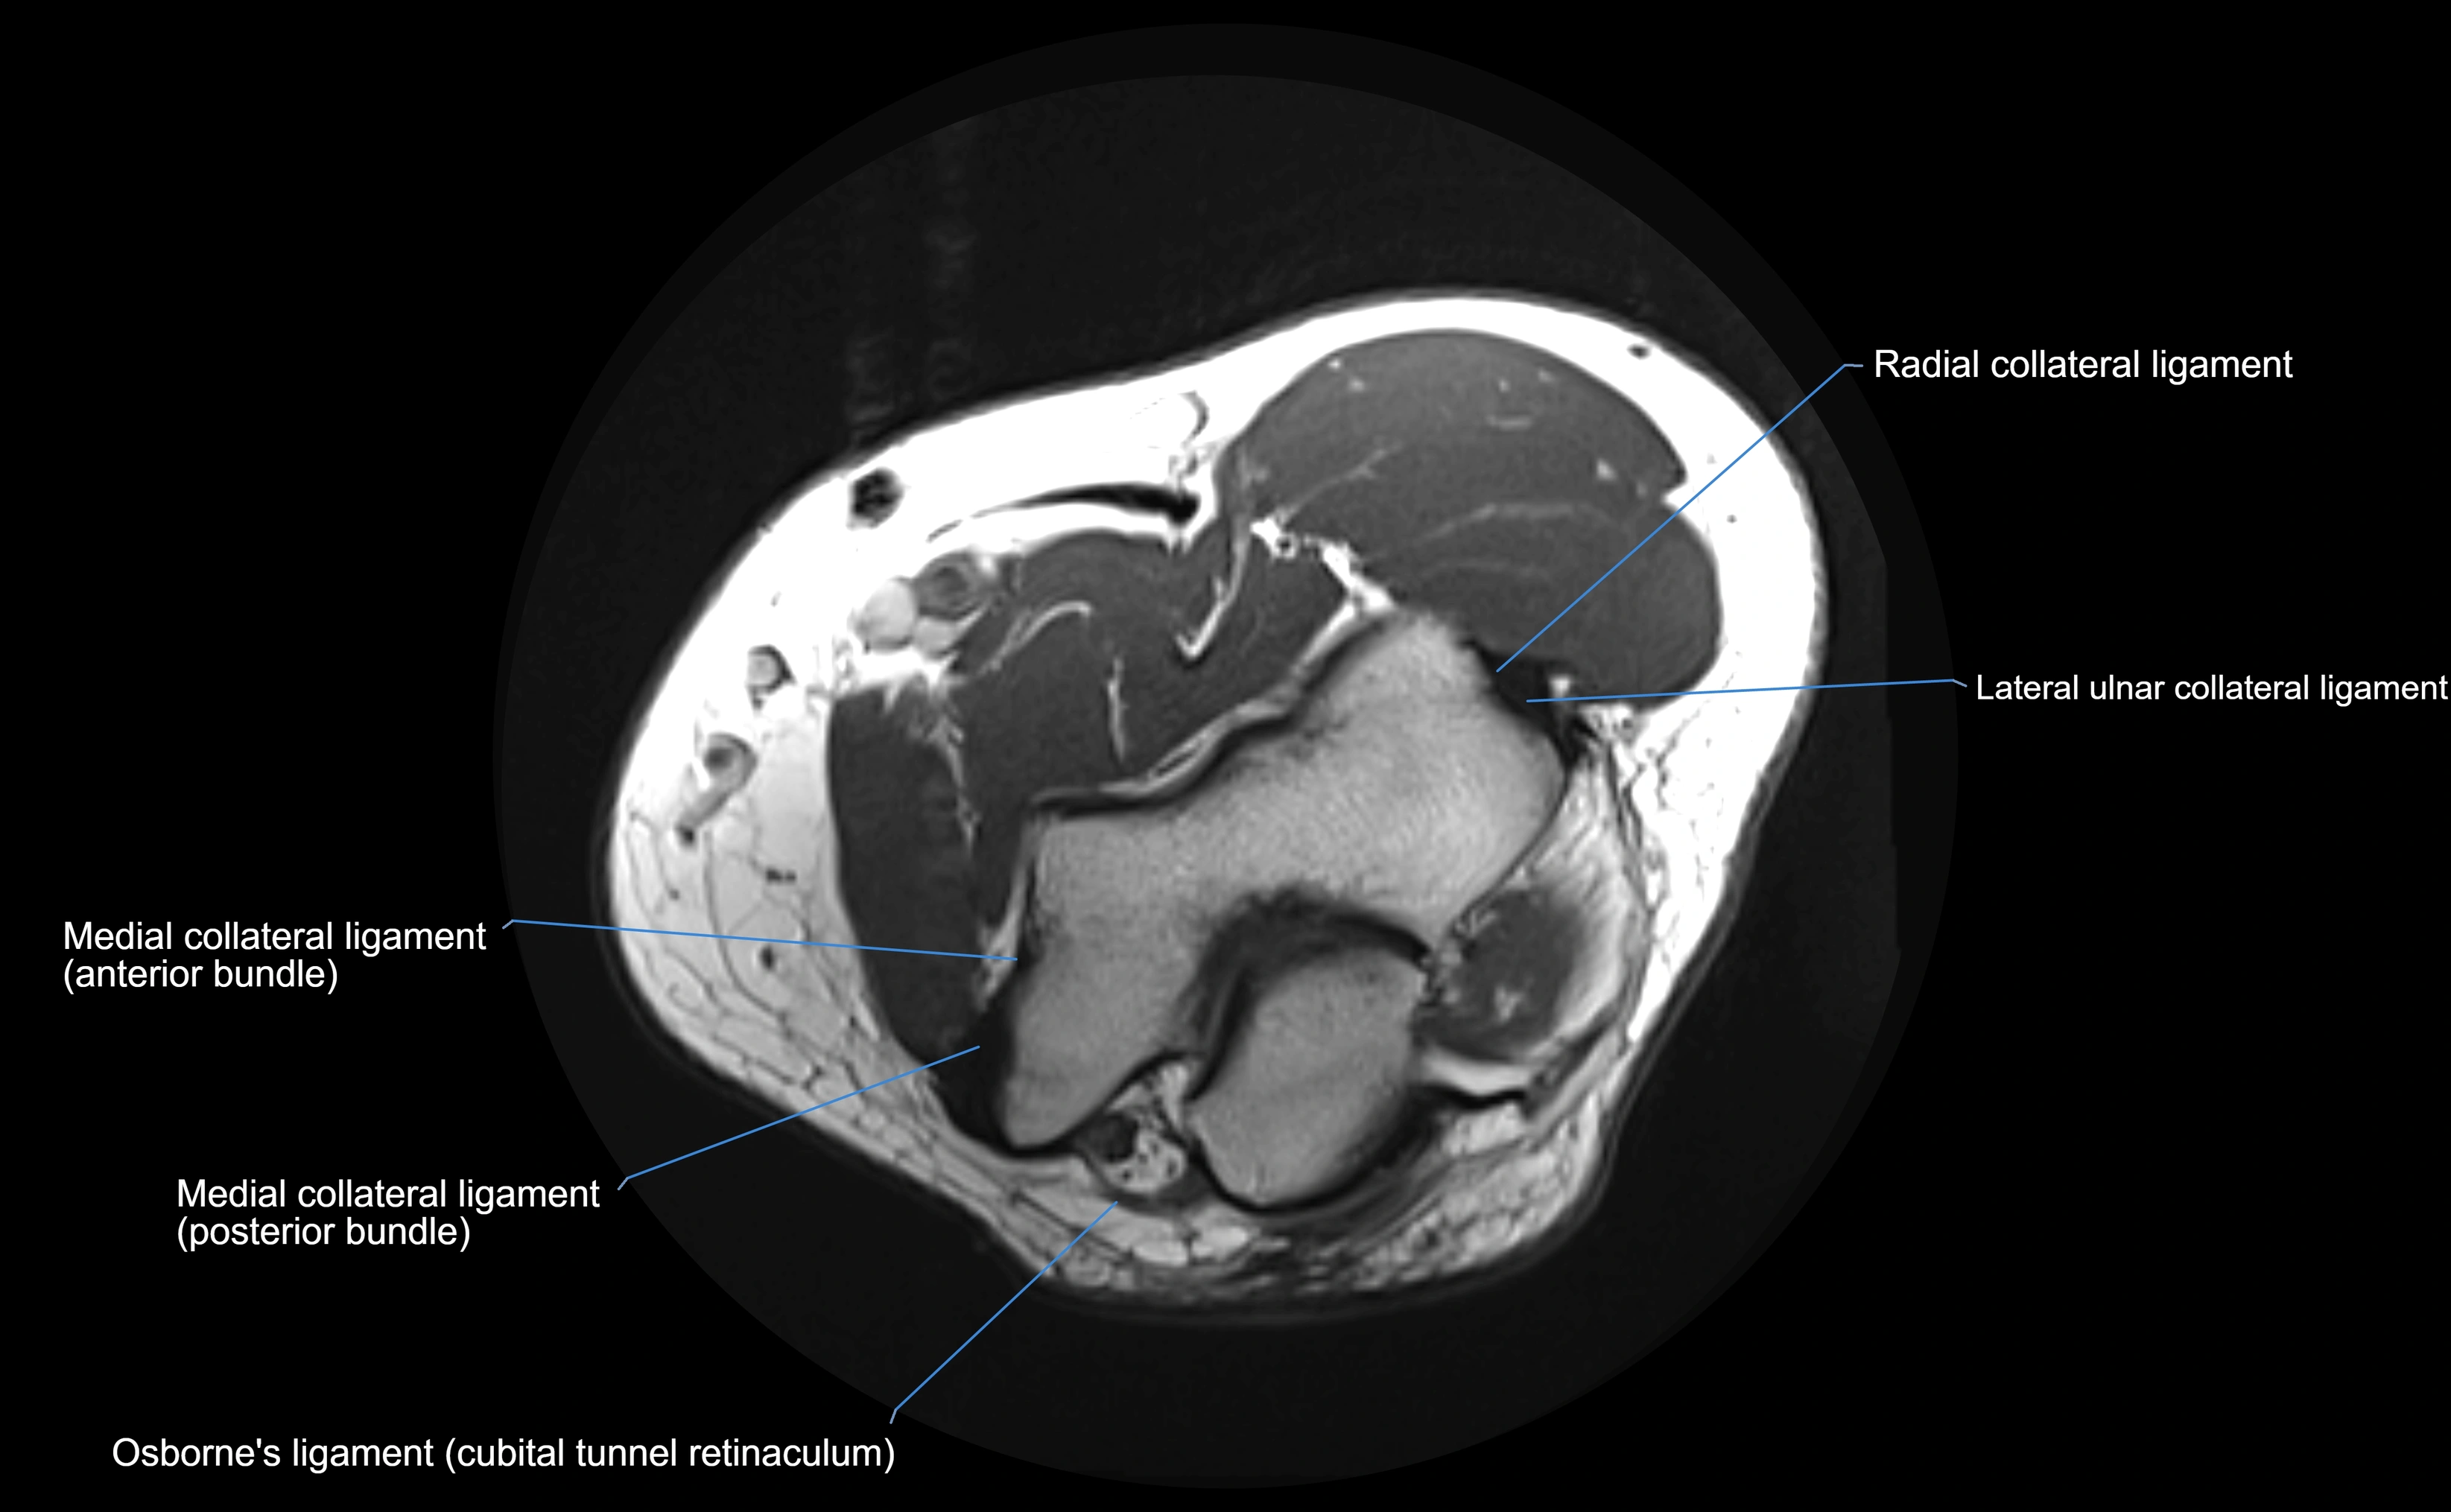

MRI images

image